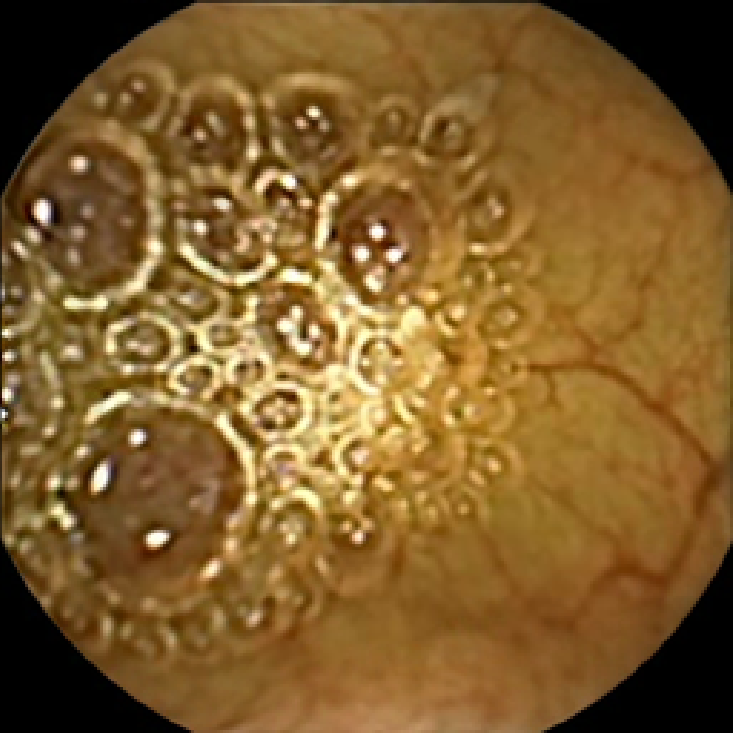

The lower bound filters out the frames with too little texture content that are unlikely to contain any polyps due to most polyps having a textured surface. The upper bound allows us to discard the frames polluted with trash and bubbles, since even if they contain polyps, they are likely to be obscured. This is illustrated in Figure 2, where we display two normal frames with low and high values of and a polyp frame with a medium value of . As expected, the first normal frame containing flat mucosa has little texture content. The second normal frame polluted with bubbles has strong texture content in the bubbles area, which is especially pronounced in the plot of . Finally, the polyp frame has moderately textured polyp area, which can also be easily observed from that has the strongest feature in that region.

The examples of incorrect classification of frames are presented in Figure 6. The first two examples show false negatives, each highlighting a possible source of classification error. The example in column (a) shows the case where the feature corresponding to the polyp was too stretched out and thus was rejected by the eccentricity criterion (21). In contrast, the feature corresponding to the polyp in column (b) has passed the combined geometric criterion (22), but the radius was below the threshold of the binary classifier. Examples in columns (c) and (d) show the two sources of possible false positives. The false positive detection in column (c) is due to insufficient illumination correction. The bright spot is not fully corrected at the pre-processing stage and subsequently generates a polyp-like feature in the mid-pass filtered frame that happens to pass through all the criteria. Finally, in column (d) a mucosal fold is classified as polyp. Note that such cases are the most difficult to deal with, as the mucosal folds can often be hard to distinguish from polyps even for a human operator.